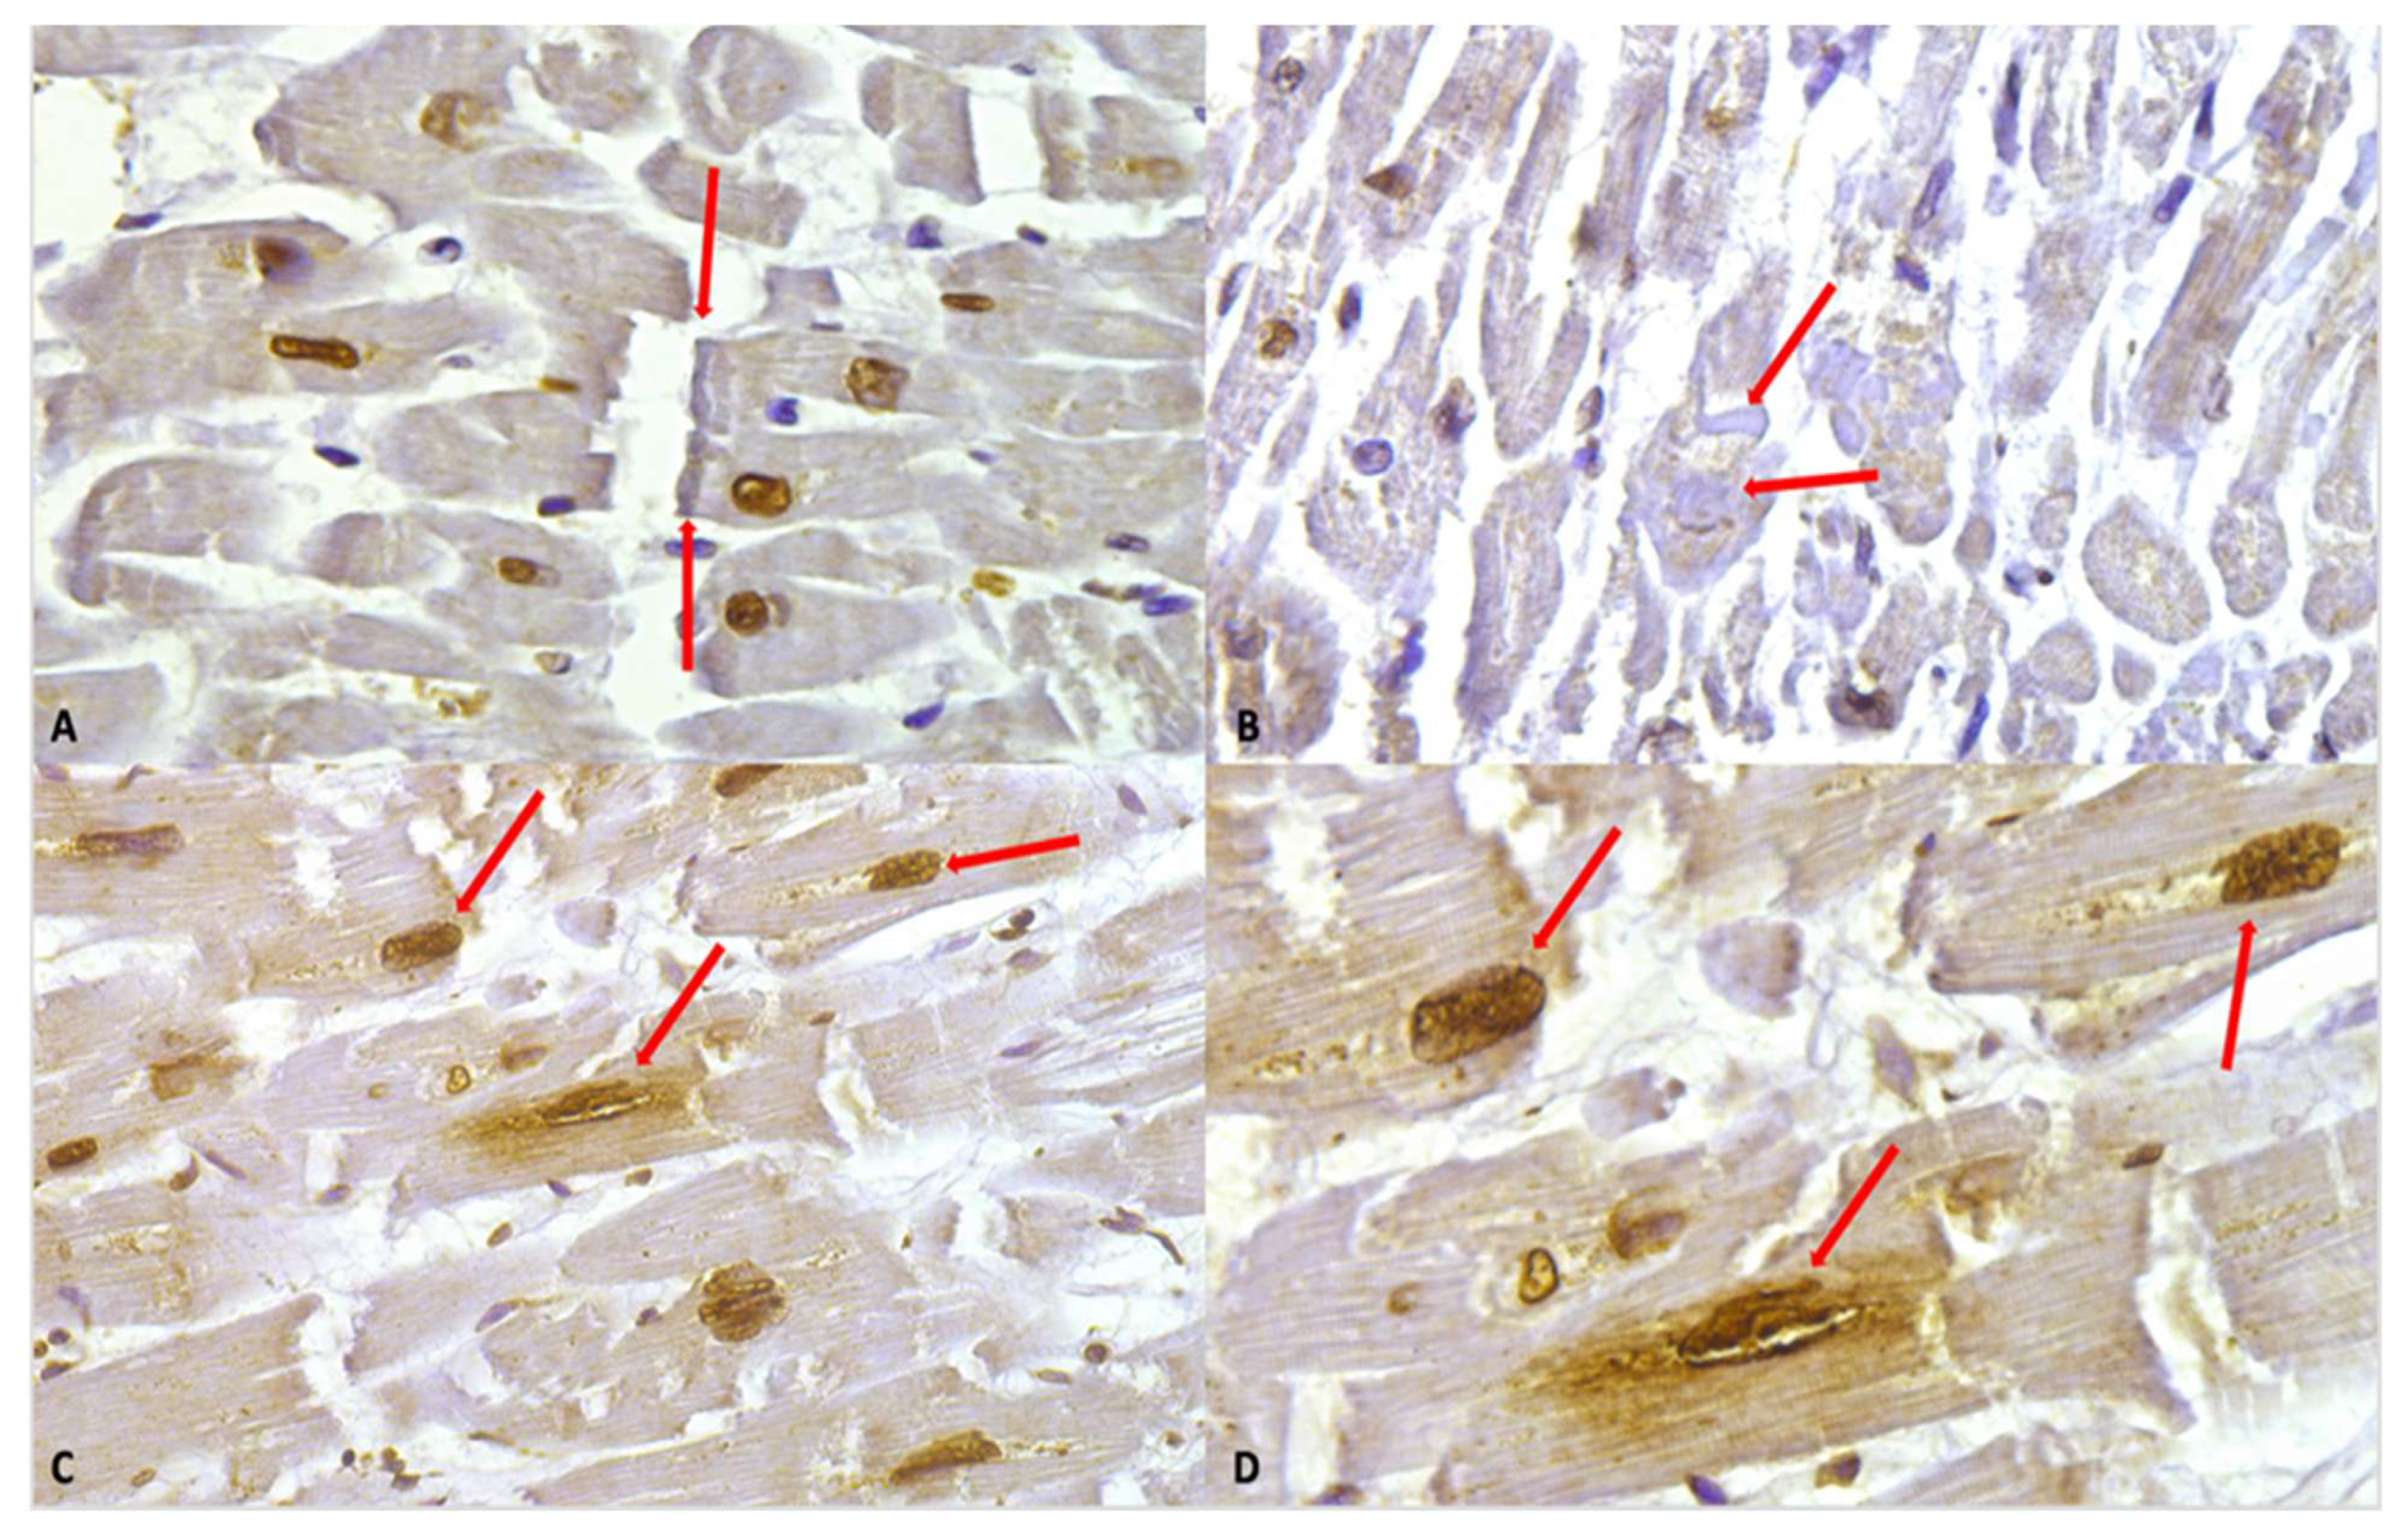

The following figure (Figure 3) illustrates the immunohistochemical expression of the anti-cocaine antibody and its various grades of expression (according to a semi-quantitative scale), along with the different alterations observed in cardiomyocytes.

Figure 3.

(A) Grade 1 (+): isolated and disseminated nuclear expression, demonstrated (red arrows) by nuclear brownish staining. 20×. (B) Grade 2 (++): expression in scattered foci. The nuclear brown reaction is more evident and intense. A slight reaction can be observed in myofibers, too. A nucleus with squaring of its edges is shown (red arrow) as a sign of cardiomyocyte damage. (C) Negative control: Any immunohistochemical reaction is shown. (D) Grade 3 (+++). Myofibrillar expression in widespread foci. The immunostaining is demonstrated by a clear brown reaction involving myofibers, compared to the negativity in the nuclei. An area of hyporeactivity in a degenerated myofiber is shown (red arrow). (E) Grade 4 (++++). Myofibrillar and nuclear widespread expression. The brown reaction is evident. Myofibrillar breakage is shown (red arrow). (F) Grade 0 (−). Negative control, magnification 40×.

The observation of heart samples from cocaine-related deaths revealed a wide range of cardiomyocyte alterations, highlighted by the positive staining.

Intense immunostaining positivity in the cardiomyocytes’ nuclei was widely observed in all tested heart samples; enlarged and square-edge nuclei were observed. This “boxcar nucleus” like shape suggests cardiac myocyte hypertrophy.

Another interesting finding was related to a peri-nuclear positive immunostaining (showing slightly less intensity compared to the nuclear one).